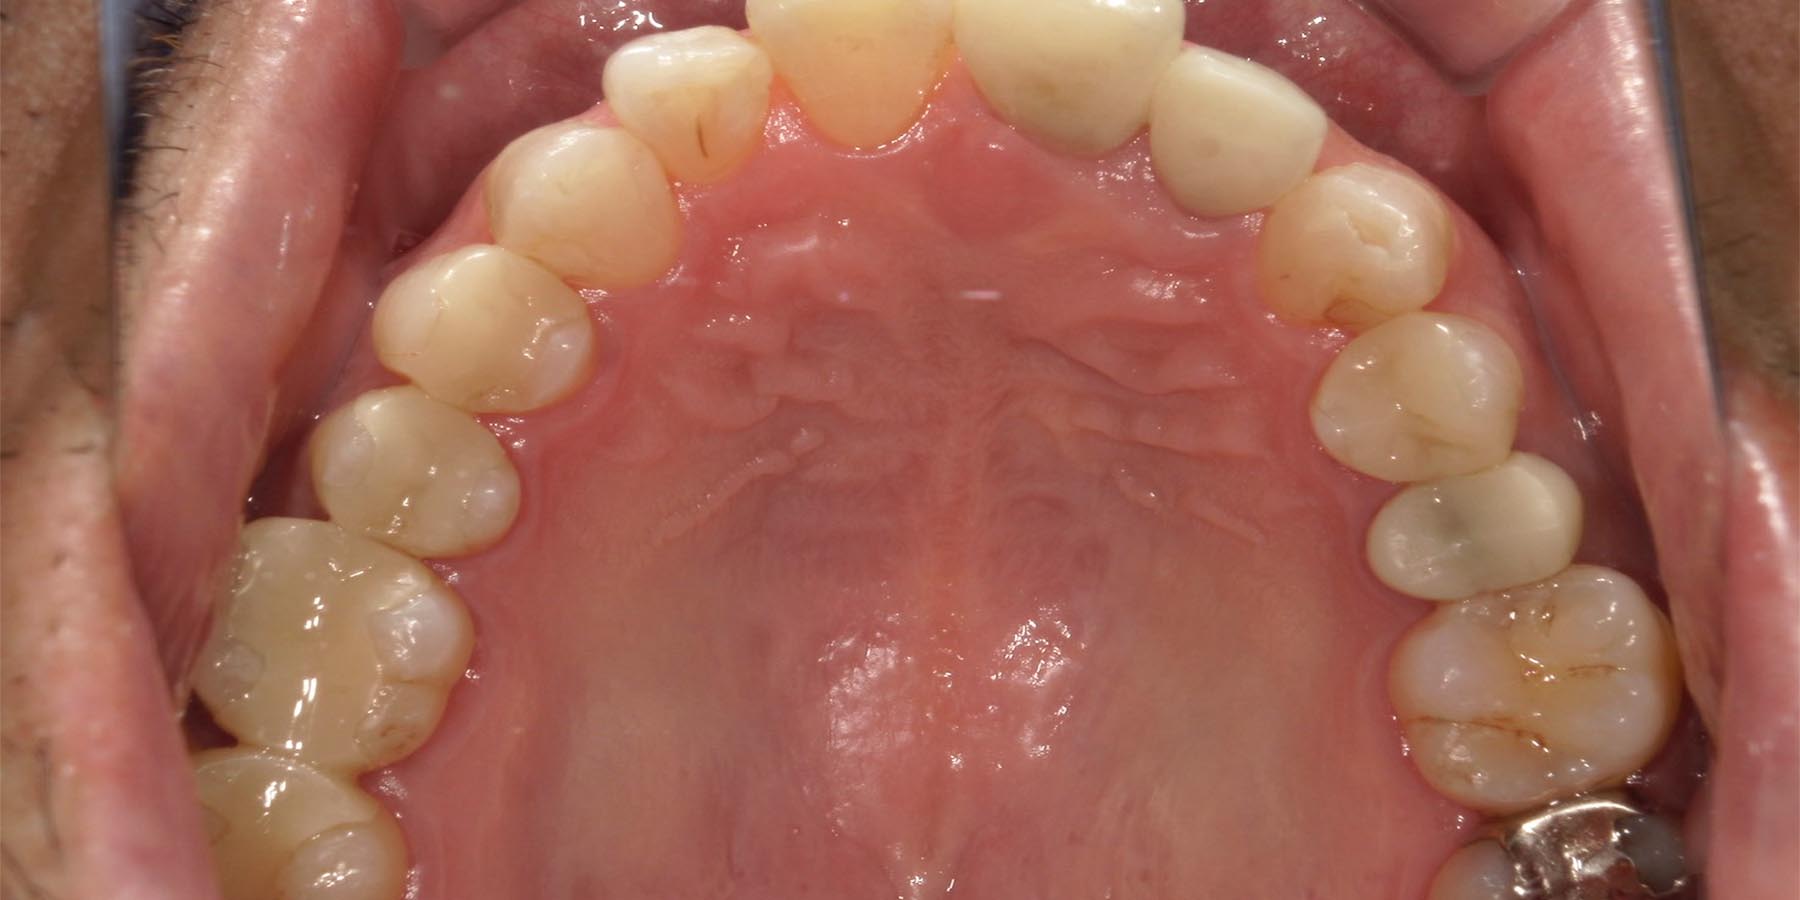

治療前